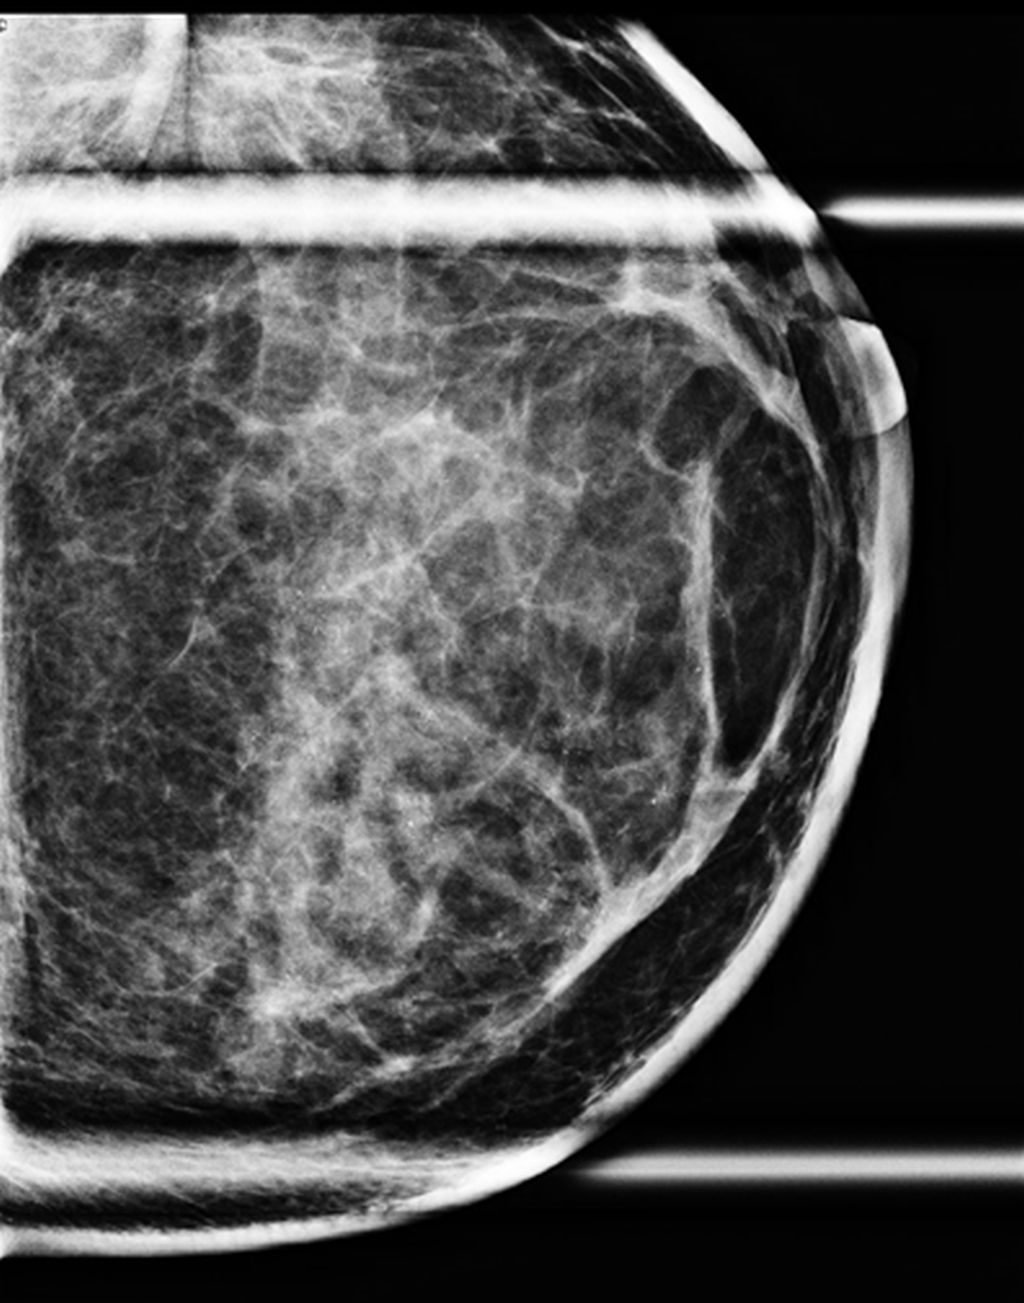

Low energy 2D mammogram images of both breasts in CC and MLO views (figure 1) demonstrate focal asymmetry with architectural distortion in the upper central quadrant of the middle third in the left breast with associated architectural distortion. Fine pleomorphic calcifications in regional distribution are noted in the inner central and upper inner quadrants of the left breast (figure 2). Diffuse skin and trabecular thickening is noted in the left breast. On post contrast recombined images (Figure 3), the area of focal asymmetry shows a heterogeneously enhancing mass with washout on delayed image (MLO). Heterogeneous and clumped non-mass enhancement in diffuse distribution is noted involving the areas of calcifications in the inner quadrant (red circle in figure 4) which could represent calcified ductal carcinoma in situ (DCIS) as well in the outer quadrant (green circle in figure 4) which could represent non-calcified DCIS. To differentiate between non-mass enhancement in diffuse distribution and background parenchymal enhancement, comparison with the opposite breast should be done. In our case there is minimal background parenchymal enhancement in the right breast (figure 3a and 3c) whereas clumped enhancement in diffuse distribution in the left breast (figure 3b and 3d) suggestive of non-mass enhancement in the left breast. Ultrasound correlation revealed an irregular isoechoic mass with indistinct margins with no posterior features measuring 2.2x1.9x1.6cm at 11:30 O'clock position, 6cm fn in left breast. It is hard on elastography (Figure 5). Non-mass ductal abnormalities in the form of irregular prominent and dilated ducts filled with soft tissue and echogenic foci within are noted in upper inner, lower inner and upper outer quadrants of left breast (Figure 6). The whole abnormality extends from the 8-12-3 o'clock position of the left breast. On tomo slices two equal density lesions with indistinct margins are noted in the upper outer quadrant of the right breast. On post contrast recombined images, they show heterogeneous enhancement. Ultrasound correlation revealed two hypoechoic lesions with circumscribed margins in the upper outer quadrant. Multiple enlarged left level I and level II lymph nodes are noted, which show asymmetrical cortical thickening and loss of fatty hilum (figure 7). MRI post contrast subtraction axial images (figure 8a and b) revealed a lesion with irregular shape and margins in the upper central quadrant of left breast with associated non-mass enhancement in diffuse distribution in upper inner, upper outer and lower inner quadrants confirming the mammographic extent of abnormalities (figure 8c).